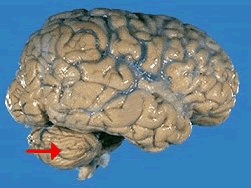

如图箭头所示为大脑哪个部位()<img border="0" style="width: 299px; height: 224px;" src="

[单选题]如图箭头所示为大脑哪个部位()A.前连合B.透明隔C.室间孔D.穹窿E.中脑导水管